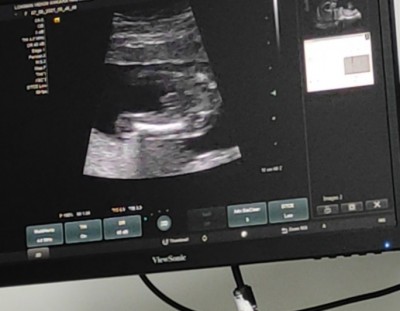

Cinsiyet tahmini yapabilen varmı

Bacak arası dolu erkek gibi geldi ama tahmin sadece

Evet erkek demisti

Çok net bir şekilde Erkek

:) doktorumda öyle dedi ben hala kordonsa belki diye umitliyim kız icin

Erkek sanki cnm

Pipisi var :)

erkek bariz belli oluyo benim oglusunkide boyle